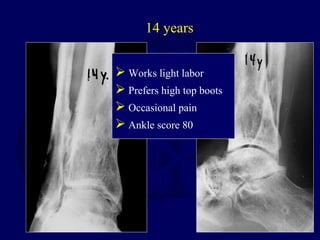

1986 - 24 yo Male

14 years

 Works light labor

 Prefers high top boots

 Occasional pain

 Ankle score 80